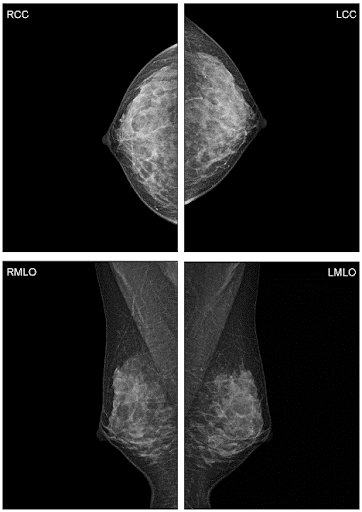

Шаг 3. Формат приемника рентгеновского изображения

В маммографии существует два общепринятых формата приемника рентгеновского изображения: 18х24 см и 24х30 см. На приемнике 18х24 см одномоментно (за одну экспозиции, без дополнительной укладки) можно исследовать грудь приблизительно до 2 размера включительно, а на приемнике 24х30 см - до 5 размера включительно.

Простой пример: во время скринингового обследования исследуют обе молочные железы в двух проекция (прямой и косой), если молочная железа целиком помещается на приемник, то делают четыре снимка, если молочную железу приходится снимать в два этапа, то делают уже 8 снимков.

◄ прямая проекция (кранио-каудальная) – CC (КК)

◄ косая проекция (медио-латеральная) – MLO (МЛК)